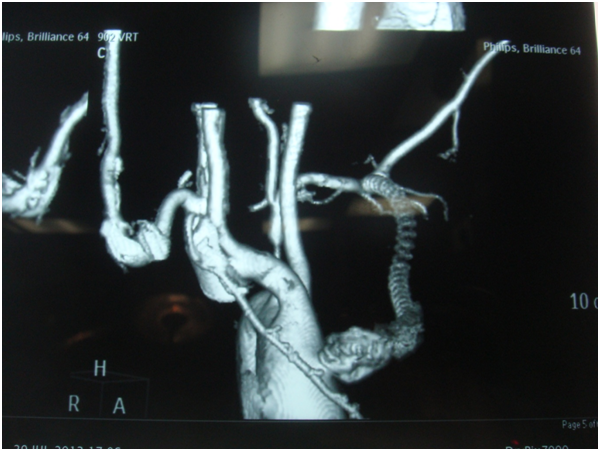

A 55 years old gentleman came to our hospital with discharging chest wound with occasional bleeding through upper chest wound. He was also suffering from fever occasionally. One and half years back he was operated in another hospital with CABG with Aorto-axillary bypass. On 4th postoperative day he needs reopening for mediastinal bleeding and needed a long ICU stay. Then he developed above mentioned symptoms. 5 days back he developed severe bleeding and was treated conservatively in another hospital. After admission CT angiogram was done-showed-Aorto-axillary bypass graft penetrating sternum and developed a leak in the aortic side. We decided for urgent operation on next day on 1.08.13-we went to femoro-femoral bypass first [1].

Figure 2: Aorto-axillary bypass-showing leak and eroding sternum.